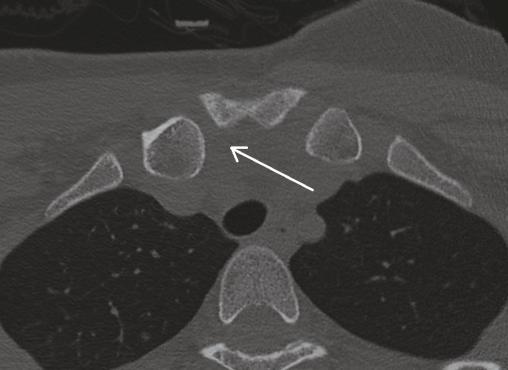

Ce dernier, réalisé deux semaines après le traumatisme, objective une subluxation postérieure de l’articulation sternoclaviculaire droite avec pincement relatif de l’interligne (fig. 2 ). Une réduction est donc réalisée.

Ce dernier, réalisé deux semaines après le traumatisme, objective une subluxation postérieure de l’articulation sternoclaviculaire droite avec pincement relatif de l’interligne (